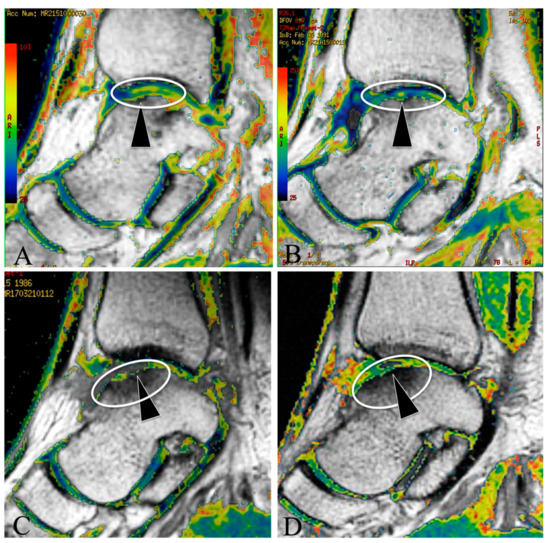

The Efficacy of Microfracture Combined with Extracorporeal Shock Wave Therapy for Treating Osteochondral Lesion of the Talus and the Quality of Regenerated Cartilage: A Retrospective Cohort Study and MRI Assessment

by Jian Li, Qiaozhi Ma, Jianlei Hou, Yufen Liu, Pengfei Lu, Pengwei Liu, Zhongwen Zhang and Gengyan Xing

J. Clin. Med. 2023, 12(8), 2966; https://doi.org/10.3390/jcm12082966 - 19 Apr 2023

Cited by 4 | Viewed by 3435

Abstract

Background: osteochondral lesion of the talus (OLT) is a common disease in the physically active population, and extracorporeal shock wave therapy (ESWT) is a noninvasive treatment. We hypothesized that microfracture (MF) combined with ESWT may have great potential to become a novel combination [...] Read more.

Background: osteochondral lesion of the talus (OLT) is a common disease in the physically active population, and extracorporeal shock wave therapy (ESWT) is a noninvasive treatment. We hypothesized that microfracture (MF) combined with ESWT may have great potential to become a novel combination treatment of OLT. Methods: the OLT patients who received MF + ESWT or MF + platelet-rich plasma (PRP) injection were retrospectively included, with a minimal follow up of 2y. The daily activating VAS, exercising VAS, and American Orthopedic Foot and Ankle Society Ankle-Hindfoot Score (AOFAS) were used to assess the efficacy and functional outcome, and ankle MRI T2 mapping was used to evaluate the quality of regenerated cartilage in the OLT patients. Results: only transient synovium-stimulated complications were found during the treatment sessions; the complication rate and daily activating VAS did not have differences between groups. MF + ESWT had a higher AOFAS and a lower T2 mapping value than MF + PRP at the 2y follow up. Conclusions: the MF + ESWT had superior efficacy for treating OLT, which resulted in better ankle function and more hyaline-like regenerated cartilage, superior to the traditional MF + PRP. Full article

(This article belongs to the Section Orthopedics)

Show Figures